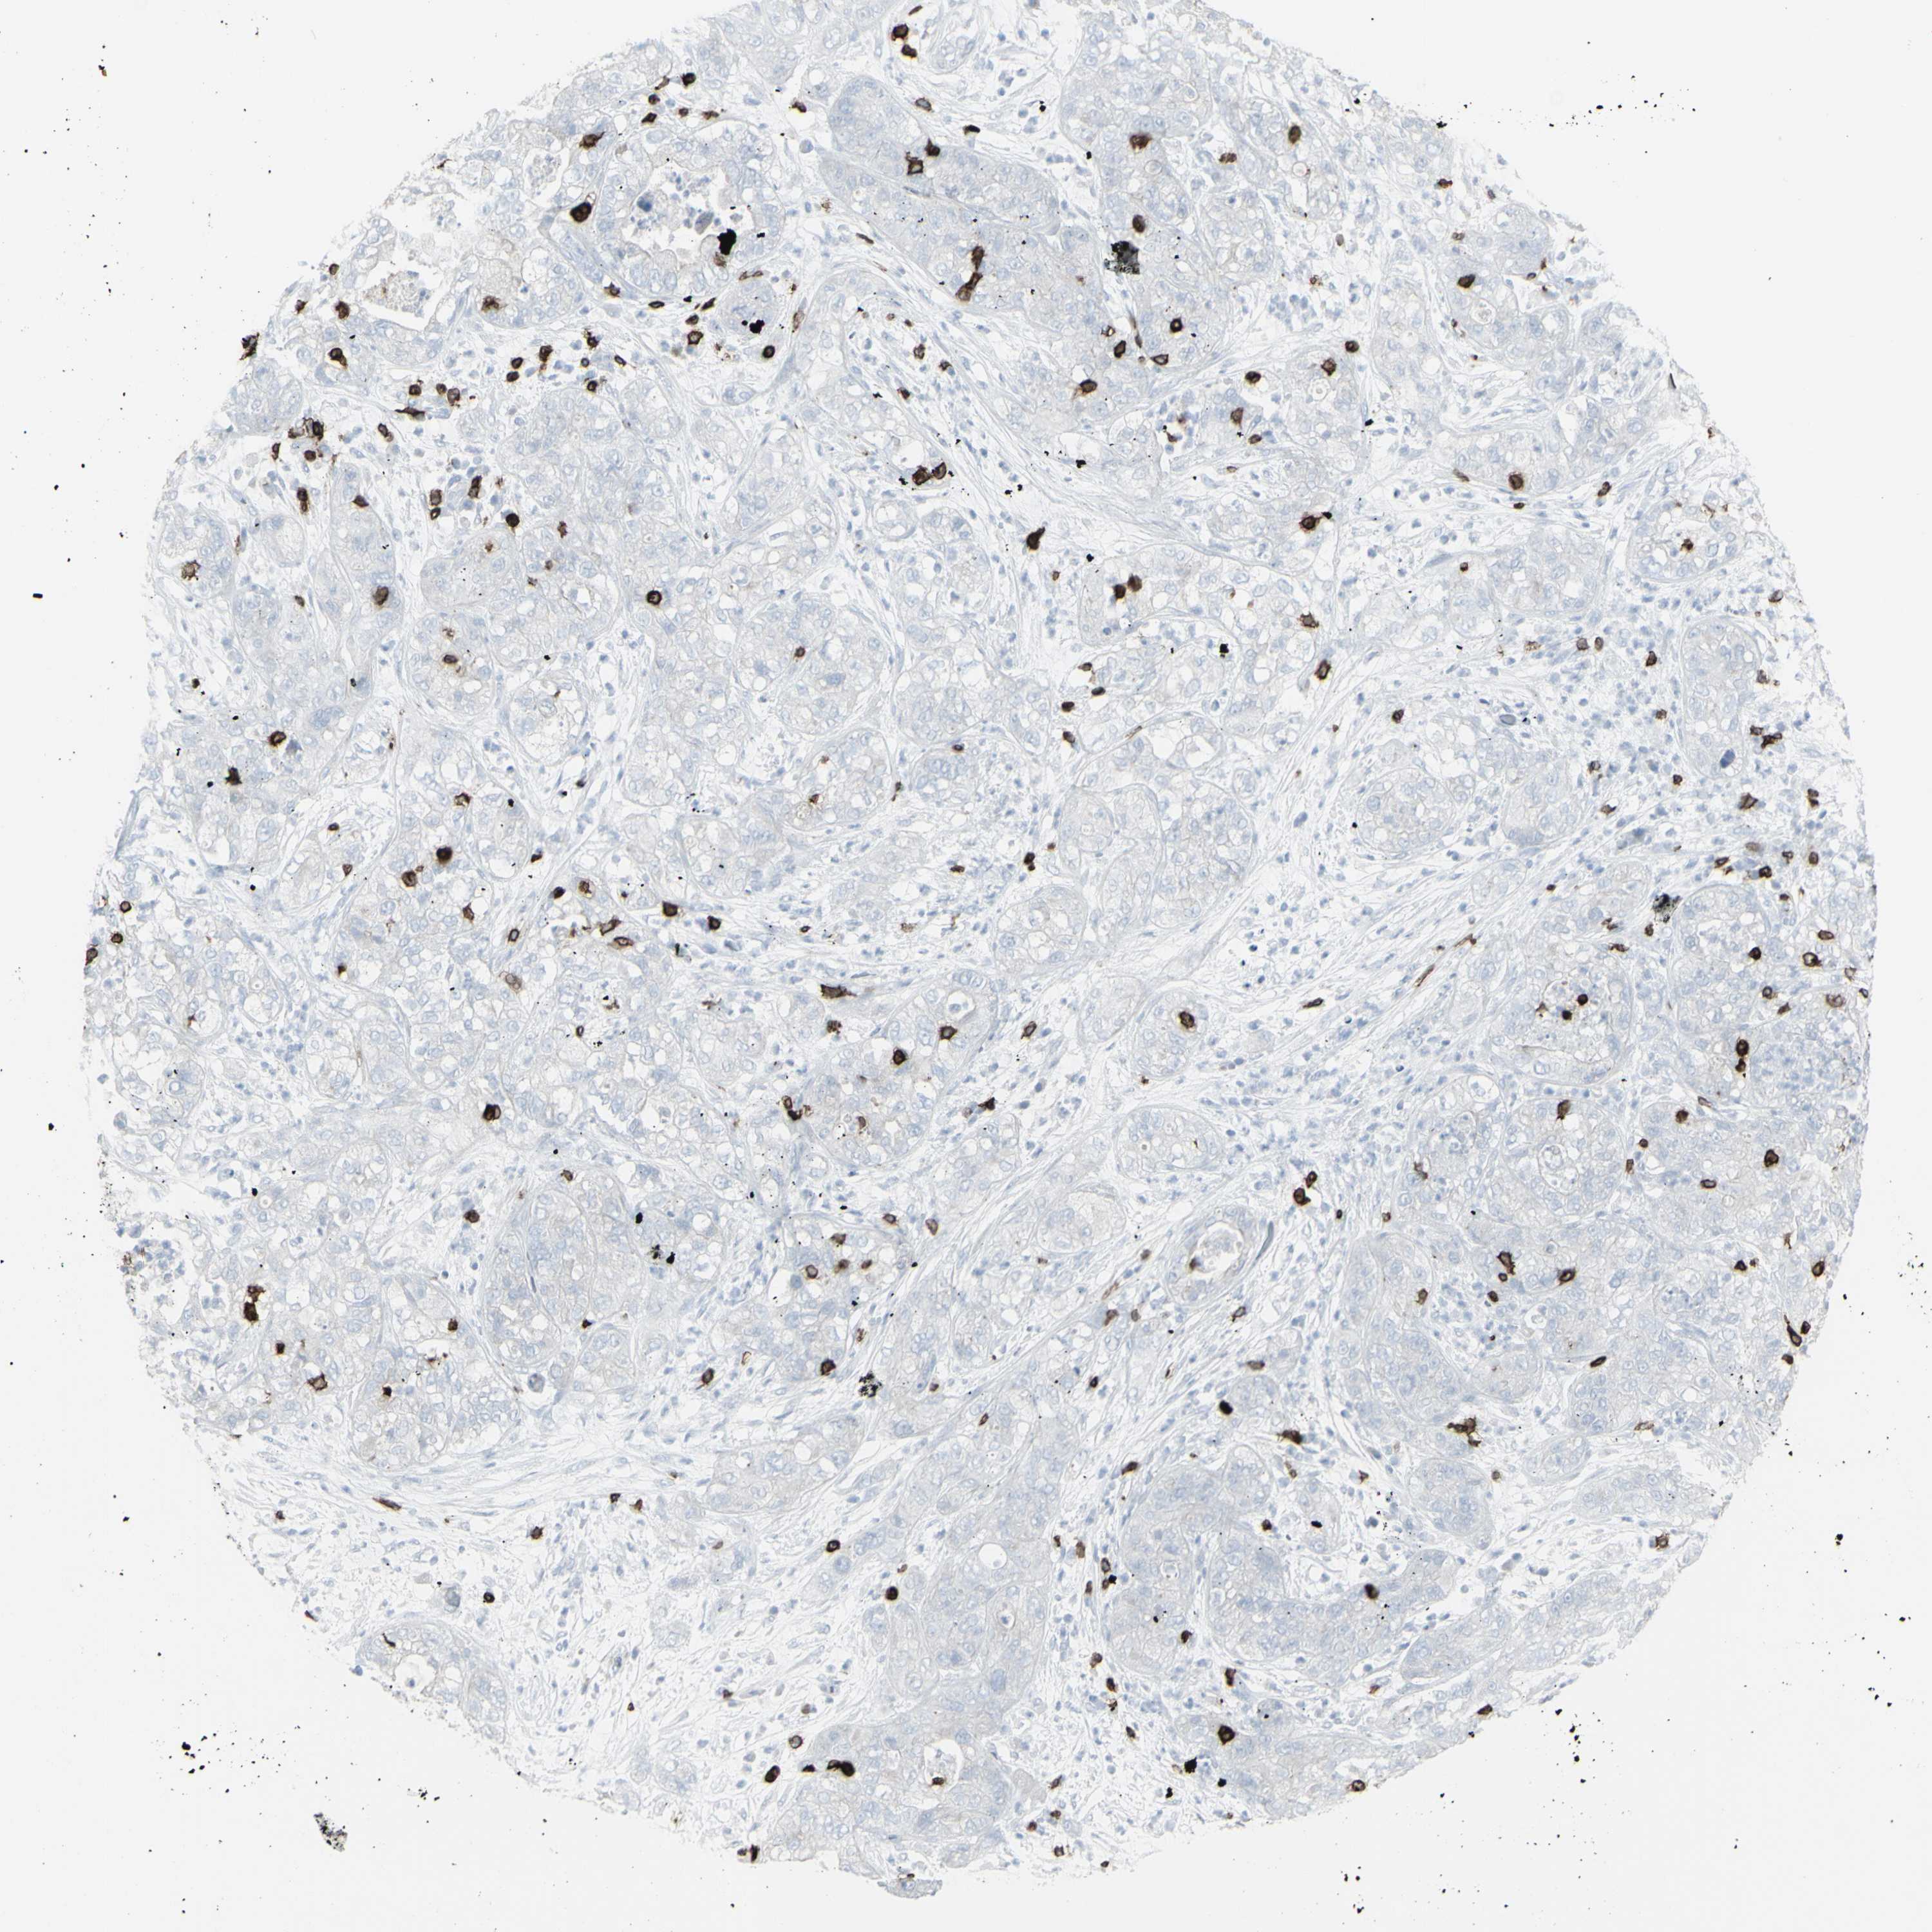

PANCREATIC CANCER - Protein expressioni

A mouse-over function shows sample information and annotation data. Click on an image to view it in a full screen mode. Samples can be filtered based on level of antibody staining by selecting one or several of the following categories: high, medium, low and not detected. The assay and annotation is described here.

Note that samples used for immunohistochemistry by the Human Protein Atlas do not correspond to samples in the TCGA dataset.

Antibody stainingi

Antibody staining in the annotated cell types in the current human tissue is reported as not detected, low, medium, or high, based on conventional immunohistochemistry profiling in selected tissues. This score is based on the combination of the staining intensity and fraction of stained cells.

Each image is clickable and will lead to virtual microscopy that enables deeper exploration of all samples and also displays staining intensity scores, fraction scores and subcellular localization as well as patient and tissue information for each sample.

Antibody HPA008750

Antibody CAB004651

Staining

High

Medium

Low

Not detected

Intensity

Strong

Moderate

Weak

Negative

Quantity

>75%

75%-25%

<25%

None

Location

Nuclear

Cytoplasmic/membranous

Cytoplasmic/membranous,nuclear

Adenocarcinoma, NOS

Adenocarcinoma, metastatic, NOS